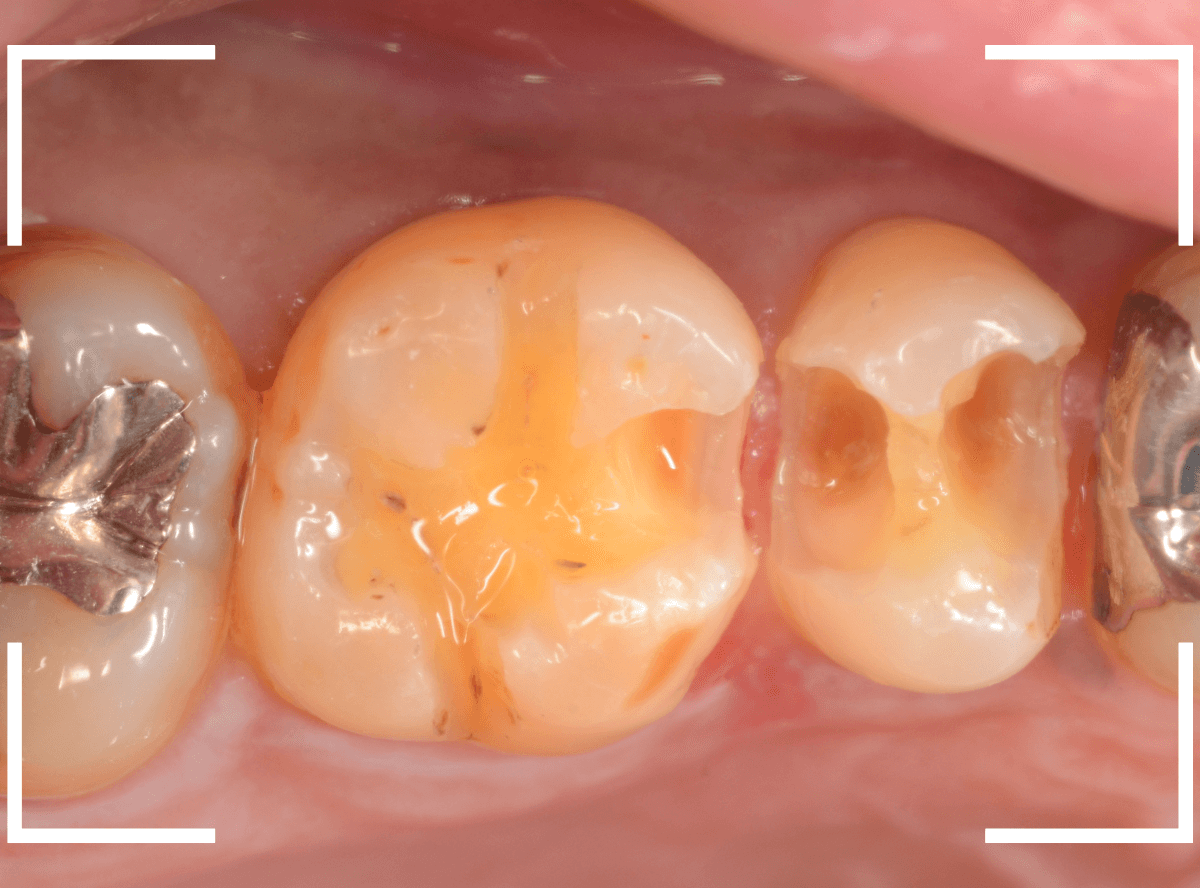

Case.24 レジンの下で虫歯が進行

上の奥歯の虫歯が見つかった患者さんです。

初診のチェックの際に、上から目視すると、レジンがつめてある〇部分が薄暗く黒くなっているので、これは虫歯があるな、とわかりました。

レントゲン写真で確認します。

赤いラインが虫歯と思われる部分、青いラインが歯の神経です。

先ほどの〇部分は明らかな虫歯になっているのがわかります。

この辺りはレジンがつめてありますが、その下もうっすらと虫歯になっていそうです。

治療を開始します。

先ほどの黒く見えた部分は少し削るとすぐに虫歯が出てきました。

手前の歯まで虫歯を除去した時点で、う蝕検知液で確認します。

赤く染色されている部分が虫歯です。

思ったよりも深めの虫歯ですね。

レジンを除去して虫歯をすべて治療したところです。

レジンの中も全体にうっすらと虫歯になっていました。

このくらいの虫歯でも、患者さんは自覚症状はありませんでした。

ご自身の自覚症状だけでは、虫歯の状況がわからないですし、自然に虫歯が治る事もありません。

いつものお話ですが、定期的なメンテナンスで、虫歯の早期発見・治療を心がけましょう。